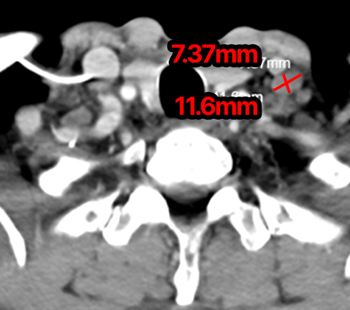

2025.1.16 CT

2025.4.9 CT

20日集中 高频热疗 实施